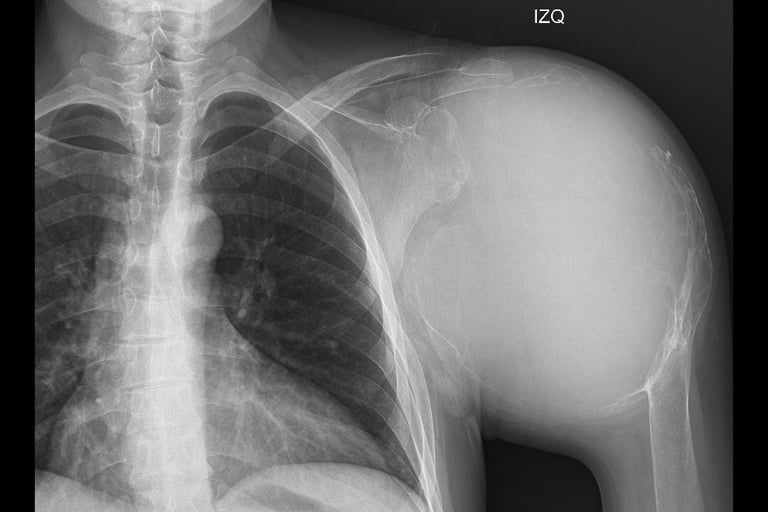

Atención especializada en traumatología y ortopedia para lesiones del sistema musculoesquelético, con alta especialidad en ortopedia oncológica para el manejo de tumores musculoesqueléticos

Conoce acerca de los padecimientos que tratamos, tanto ortopedicos, traumatológicos y ortopedicos oncológicos.

Ofrecemos los tratamientos especializados y personalizados, con enfoque integral multidisciplinario.